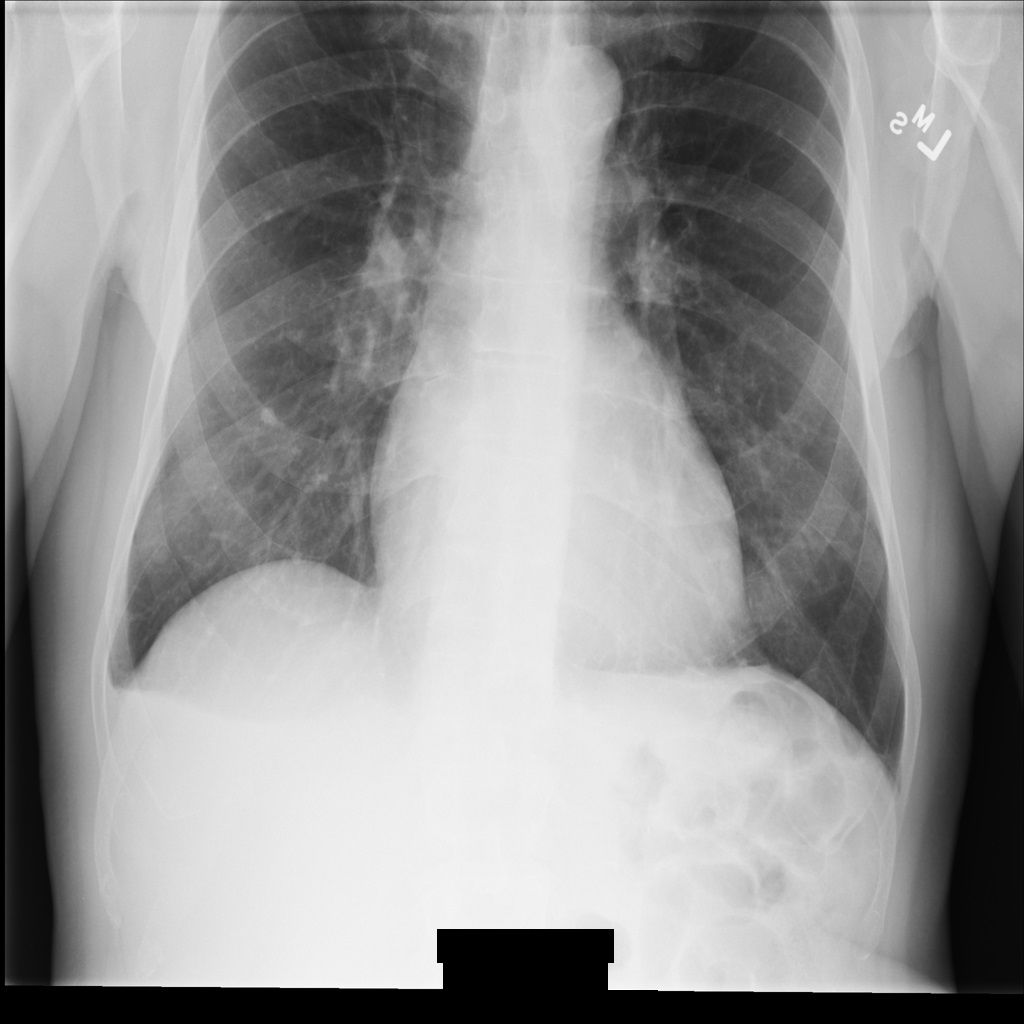

En las siguientes secciones se muestra el aspecto de la imagen de la instancia DICOM y los metadatos de la instancia.

Imagen de muestra

Algunas muestras de esta página contienen el resultado de la imagen anonimizada. En cada ejemplo se usa la siguiente imagen original como entrada. Puedes comparar la imagen de salida de cada operación de anonimización con la imagen original para ver los efectos de la operación:

xray_original